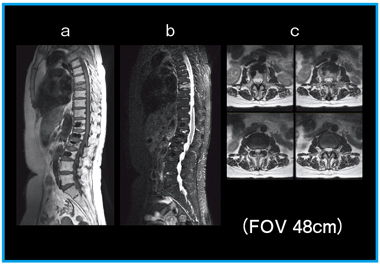

●骨軟部系(図2)

上下方向に歪みのない,良好な画像が撮像できる。

図2 経皮的椎体形成術後の圧迫骨折

a:T1強調画像 (サジタル画像,スキャン時間2分25秒)

b:T2強調画像 (IDEAL,FatSAT,スキャン時間3分18秒)

c:T2強調画像 (アキシャル画像,スキャン時間2分26秒)